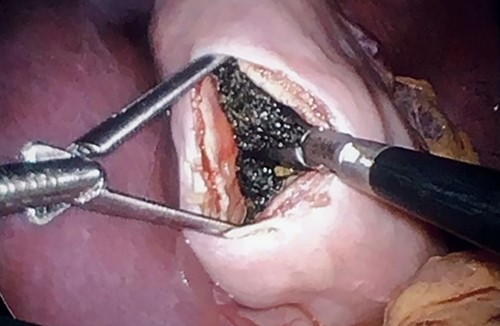

Therefore, the family was consulted about removing the bezoar surgically. The procedure was performed laparoscopically with three working ports: two working 5-mm ports and one 11-mm camera port. A 5-cm gastrostomy at the body of the stomach was done (Fig. 2). A large bezoar was found at the pylorus, extending to the duodenum. The large bezoar was removed with an endo grasper, and the stomach was closed with a Vicryl suture. An Endo-leak test was performed, and the specimen was removed from the umbilical port with an endo bag. The bezoar was extracted with no spillage in the abdominal cavity, and none remained in the stomach (Fig. 3).